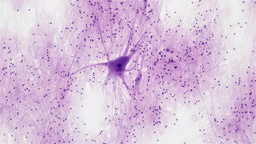

The fight against cancer in the African-American community goes back far beyond our present day. Besides just disproportionately affecting this community of patients, the racial inequities and systemic issues seen in the research and healthcare system makes the fight that much harder. This is all encapsulated in the life story of Henrietta Lacks. During a discussion between the organizing committee about the setup of the days of #BlackinCancerWeek, we knew we wanted to celebrate “The Mother of Modern Medicine.” Her contribution, HeLa cells, which were stolen and propagated without her knowledge, led to groundbreaking discoveries in cancer, immunology, and infectious diseases.2 Her cells are even being used now to find a vaccine for COVID-19.3 And yet, almost 70 years have passed and HeLa cells are still being used in research while the Lacks Family has yet to be indemnified for this historical wrong.